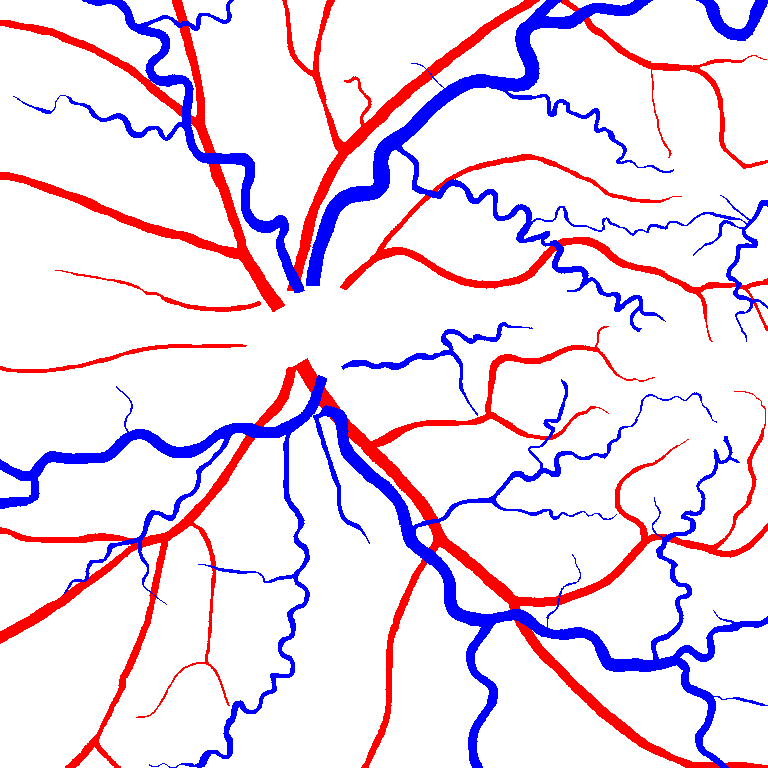

Table VI presents a quantitative comparison of the measured diameters using the segmentation outputs of SegRAVIR and competing approaches. Using the pixel-wise annotated masks, the reference average diameter of the arteries and veins in the test set of the RAVIR dataset were measured as and , respectively. According to our analysis, SegRAVIR can accurately measure the diameter of the vessels and it achieves the smallest MAPE among the competing approaches. Specifically, in comparison to CE-Net, Iter-Net, and DU-Net, respectively, SegRAVIR is on average , and more accurate in terms of MAPE for the measured diameter of arteries and , and in terms of MAPE for the measured diameter of veins. Fig. 6 presents qualitative comparisons of reference and SegRAVIR estimated diameter maps.

(a) (b) (c)